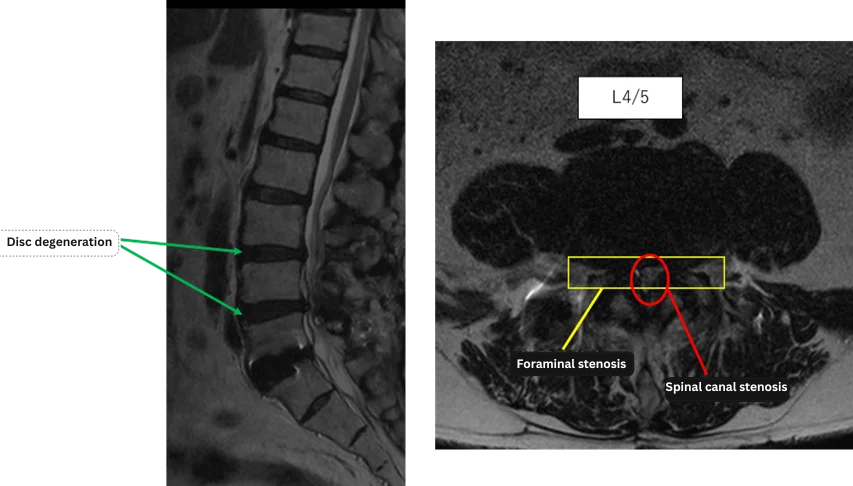

L3/4: Disc degeneration, bilateral foraminal stenosis

L4/5: Disc degeneration, bilateral foraminal stenosis, lumbar spinal canal stenosis

The above findings were also observed on the imaging.

Based on imaging, disc degeneration, bilateral foraminal stenosis, and spinal canal stenosis at L3/4 and L4/5 were identified and considered the most likely causes of the patient’s primary symptoms.